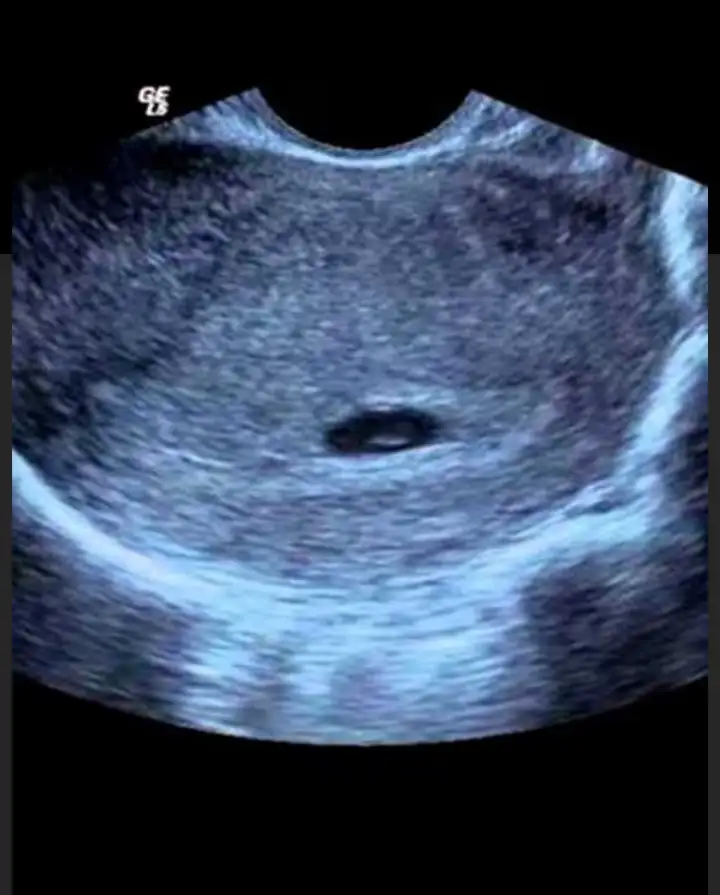

kızlaar birde kese yı gordugunuzda bebekte ıcındemı oluyor bebegı sonramı goruyoruz.,

Ilk kese sana yolladigim foto gibi oluyor noktacik icinde oluyor sonra hamilelik ilerledikce bebegin gelistikce ultrason goruntuleride buyuyecekkızlaar birde kese yı gordugunuzda bebekte ıcındemı oluyor bebegı sonramı goruyoruz.,

Canım senin kese tarihini baya ileri tarihe attıgı için sen keseyle birlikte içinde beneği de görürsün tabi net görüntü olmaz ama görünürkızlaar birde kese yı gordugunuzda bebekte ıcındemı oluyor bebegı sonramı goruyoruz.,